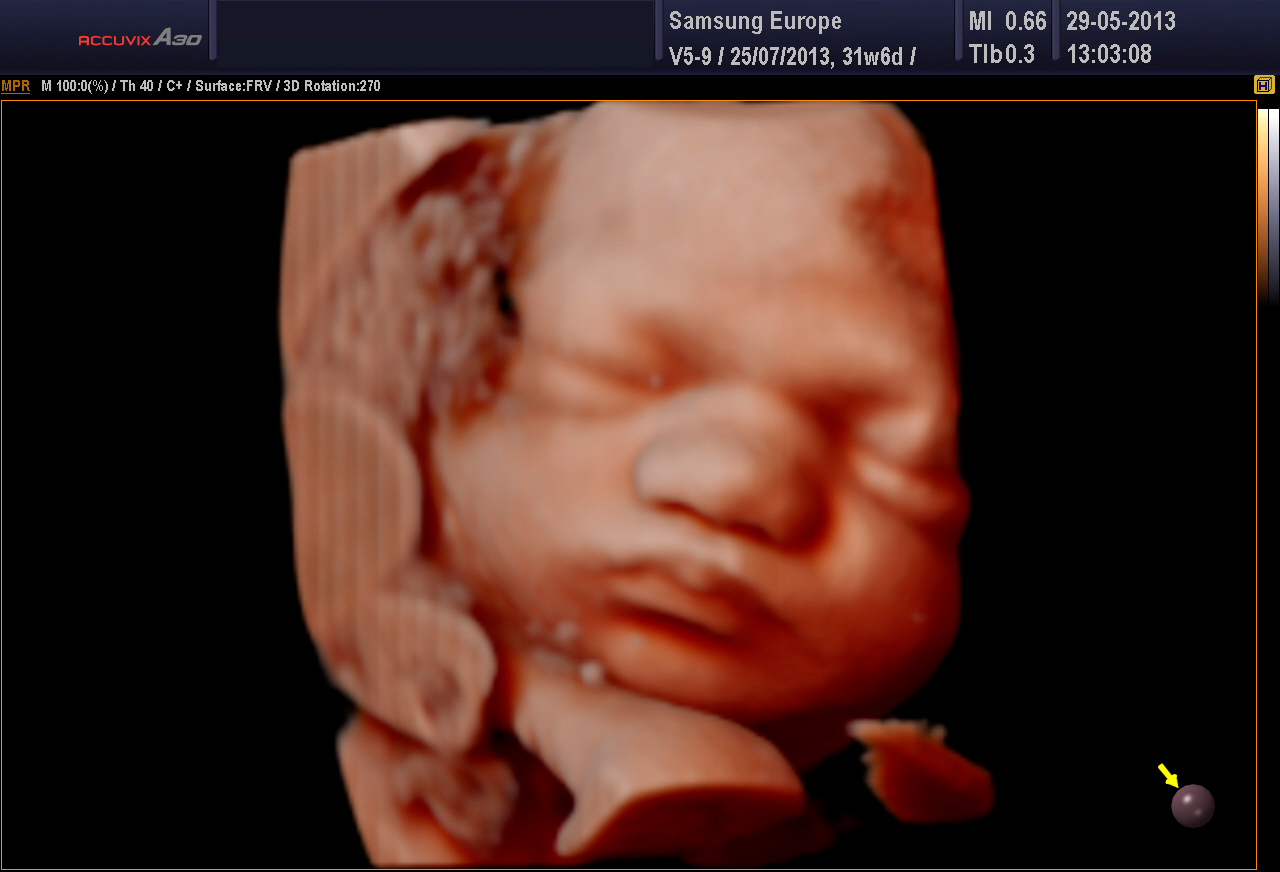

Ehdottomasti molemmat! 3D-tekniikalla tuotetaan staattista neulanterävää kolmiulotteista kuvaa. Se soveltuu sikiön kuvaamiseen, kun halutaan mahdollisimman tarkkaa ja korkealaatuista kuvaa. 4D-tekniikka on tarkoitettu erityisesti sikiön liikkuvaan ja kolmiulotteiseen kuvaamiseen.

Kuva Femedan 4D-ultraäänitutkimuksesta

3D ja 4D-tekniikat soveltuvat erityisen hyvin sikiön kasvojen anatomian tutkimiseen. Tutkimuksessa poissuljetaan mahdollinen huulihalkio ja kasvojen profiilissa esiintyvät muut poikkeamat, kuten liian pieni leuka. Samalla selvitetään korvien anatomia ja niiden sijainti. Tekniikan avulla selvitetään raajojen asennot, sekä sormien ja varpaiden lukumäärä ja niiden liikkuvuus. Lisäksi tutkitaan koko selkärangan rakenne ja suljetaan pois poikkeamat, kuten puuttuvat lapa- tai olkaluut.

4D-tutkimukset voidaan tehdään koska tahansa raskauden aikana. Sikiön rakenne voidaan selvittää kuitenkin parhaiten raskausviikoilla 19-30. Sikiön kasvonpiirteet näkyvät parhaiten raskausviikoilla 22-28. Niukka lapsiveden määrä, epäedullinen sikiön asento, äidin ylipaino tai paksut vatsanpeitteet saattavat vaikuttaa 4D-kuvien laatuun, mutta ne harvoin estävät tyydyttävän arvion saamista sikiön anatomiasta.

Sikiöstä otetut kolmiulotteiset kuvat ovat erittäin tarkkoja ja havainnollistavia – suorastaan kauniita. Kuvauksiin voi tulla millä tahansa raskausviikolla. Tutkimusta ei tarvitse pelätä ja tulevan lapsen isä ja sisarukset ovat myös lämpimästi tervetulleita. Tilanne on usein ikimuistoinen ja ainutkertainen kokemus koko perheelle.